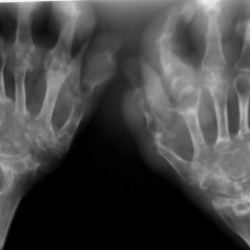

Думаю, что особых трудностей наблюдение вызвать не должно. Хотя...